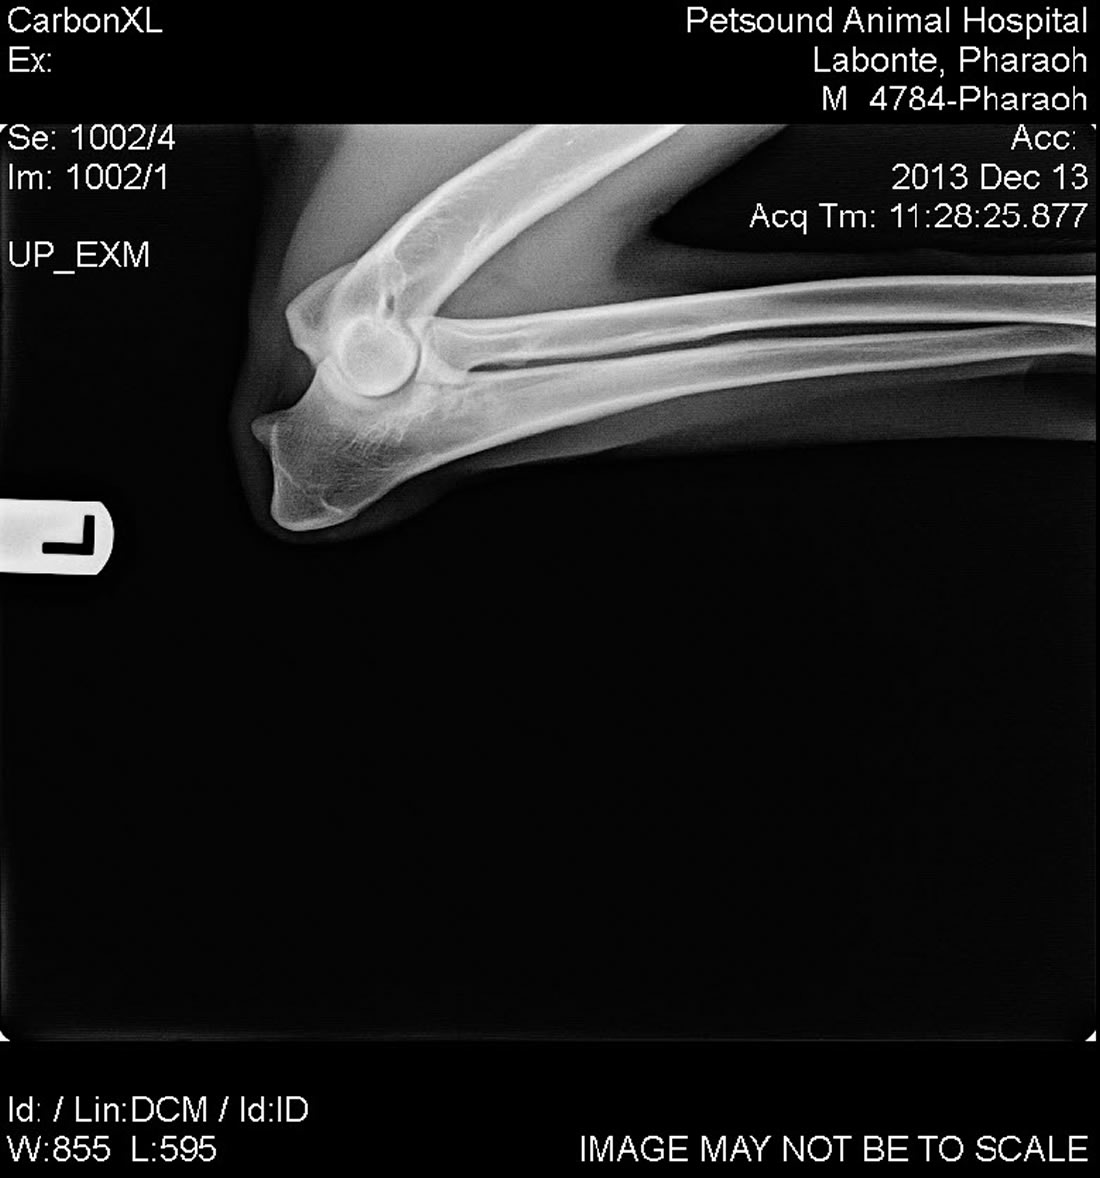

Labonte's Pharaoh - OFA Excellent

Labonte's Pharaoh - OFA Excellent is an extreme prey driven dog and is very fast with a 37mph escape. His hips have the rare OFA rating of Excellent. He is black with a very nice red color and a strong European structure. Pharoah's pedigree is nothing short of awesome. With dogs like Fero, Quinto, Orry and lines like Karthago, Antverpa, Tiekerhook, Korbelbach giving her a very well rounded foundation and strong genes for breeding.